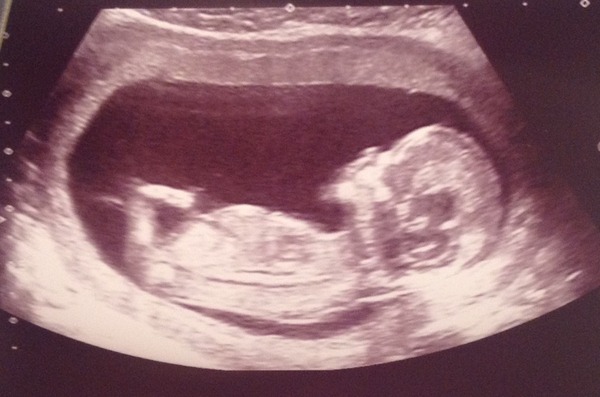

Thanks for the congrats, everyone! I was half convinced it wouldn't be okay, so I was stunned when it came up on the screen! It was so incredible... Moving around, waving its arms, touching its face and stretching its legs. We saw the heart beating away, too.

It measured 12+6, moving me on 4 days, which is quite possible because I have irregular cycles and the dates had been based on a 28 day cycle. So I'm now due on the 28th June - will update stats thread - but please let me stay here!!!

Nuchal measurement was good, just got to wait for bloods - which could take ages due to the bank holidays. If there is a problem we won't know for over a week, but hey ho.

It was such a lovely experience. I can't believe all that is going on inside me!

Bluebell aww another fab scan photo. Of course you can stay here we wouldn't want you to go.

What an amazing scan photo as well! Glad all is well with the baby, and how amazing to see it moving on the screen Smile

Such amazing pictures. My 9 week one still looks like a little blob, it's amazing how much it progresses in just a few weeks! The best bit is watching DHs face in amazement Smile can't wait for my 12 (14 Hmm week) scan...